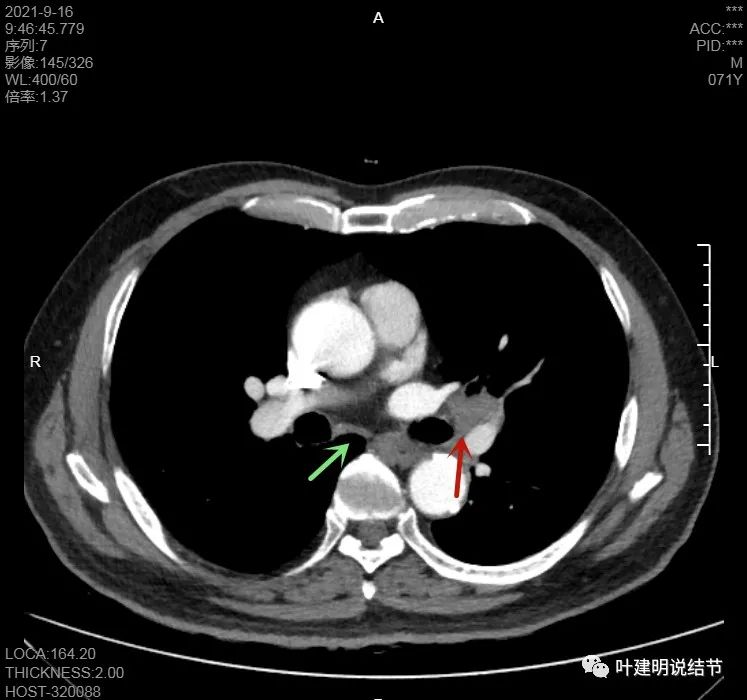

左肺门区淋巴结肿大

肺门区淋巴结挤压附近肺血管,但似乎示见肿瘤侵犯破坏血管壁

淋巴结巨大,部分包绕肺血管,但仍未见明显侵犯血管壁

肺血管受压明显,气管内壁感觉也是光滑的

以上诸图均示肿大淋巴结挤压肺血管,但未见确切侵犯破坏,支气管内壁也感觉是光滑的,没有肿瘤突向管腔